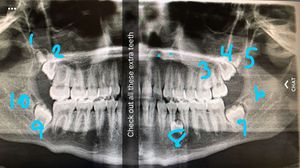

Extra extra

6 extra teeth, not including your 3rds